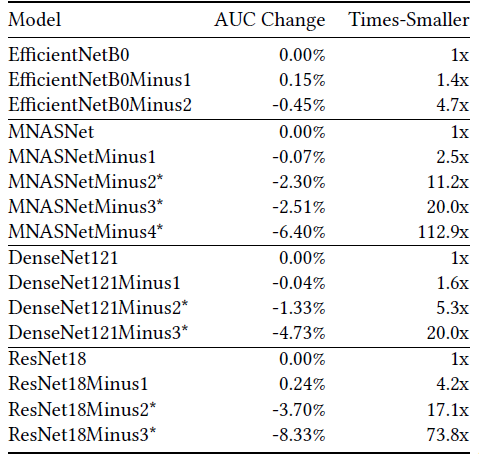

- Networks compose of repeated blocks, each block is constructed with convolutional layers.

- Performance is evaluated by truncating the blocks and appending the classification layer (Global average pooling then fully connected layer) at the end.

For all four model families, truncating the final block leads to no significant decrease in CheXpert AUC but can save 1.4× to 4.2× the parameters.